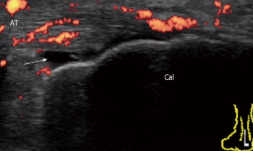

Tendon-related pain and symptoms associated with inflammation → increased vascularity

Retrocalcaneal bursitis

Partial or complete Achilles tendon tears